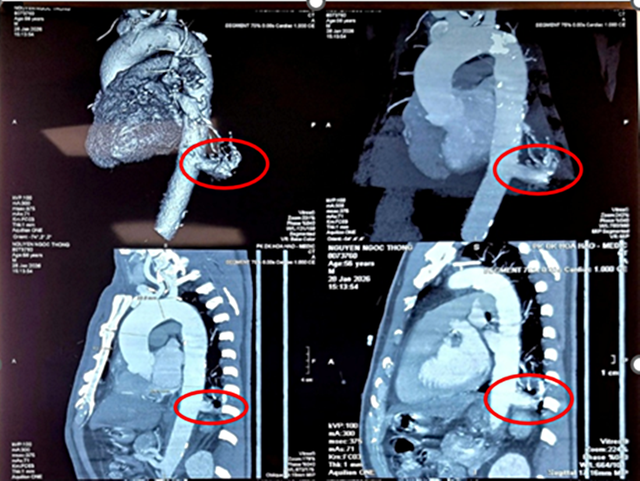

Người bệnh là ông N.N.T (56 tuổi, Tây Ninh), tình cờ phát hiện tổn thương ở thùy dưới phổi trái khi khám sức khỏe tổng quát. Kết quả chụp cắt lớp vi tính cho thấy khối phổi biệt lập kích thước 23x26mm.

Điểm đáng lo ngại là động mạch nuôi khối này xuất phát trực tiếp từ động mạch chủ ngực xuống, đường kính lên tới 17mm – kích thước lớn, tiềm ẩn nguy cơ chảy máu ồ ạt nếu vỡ.